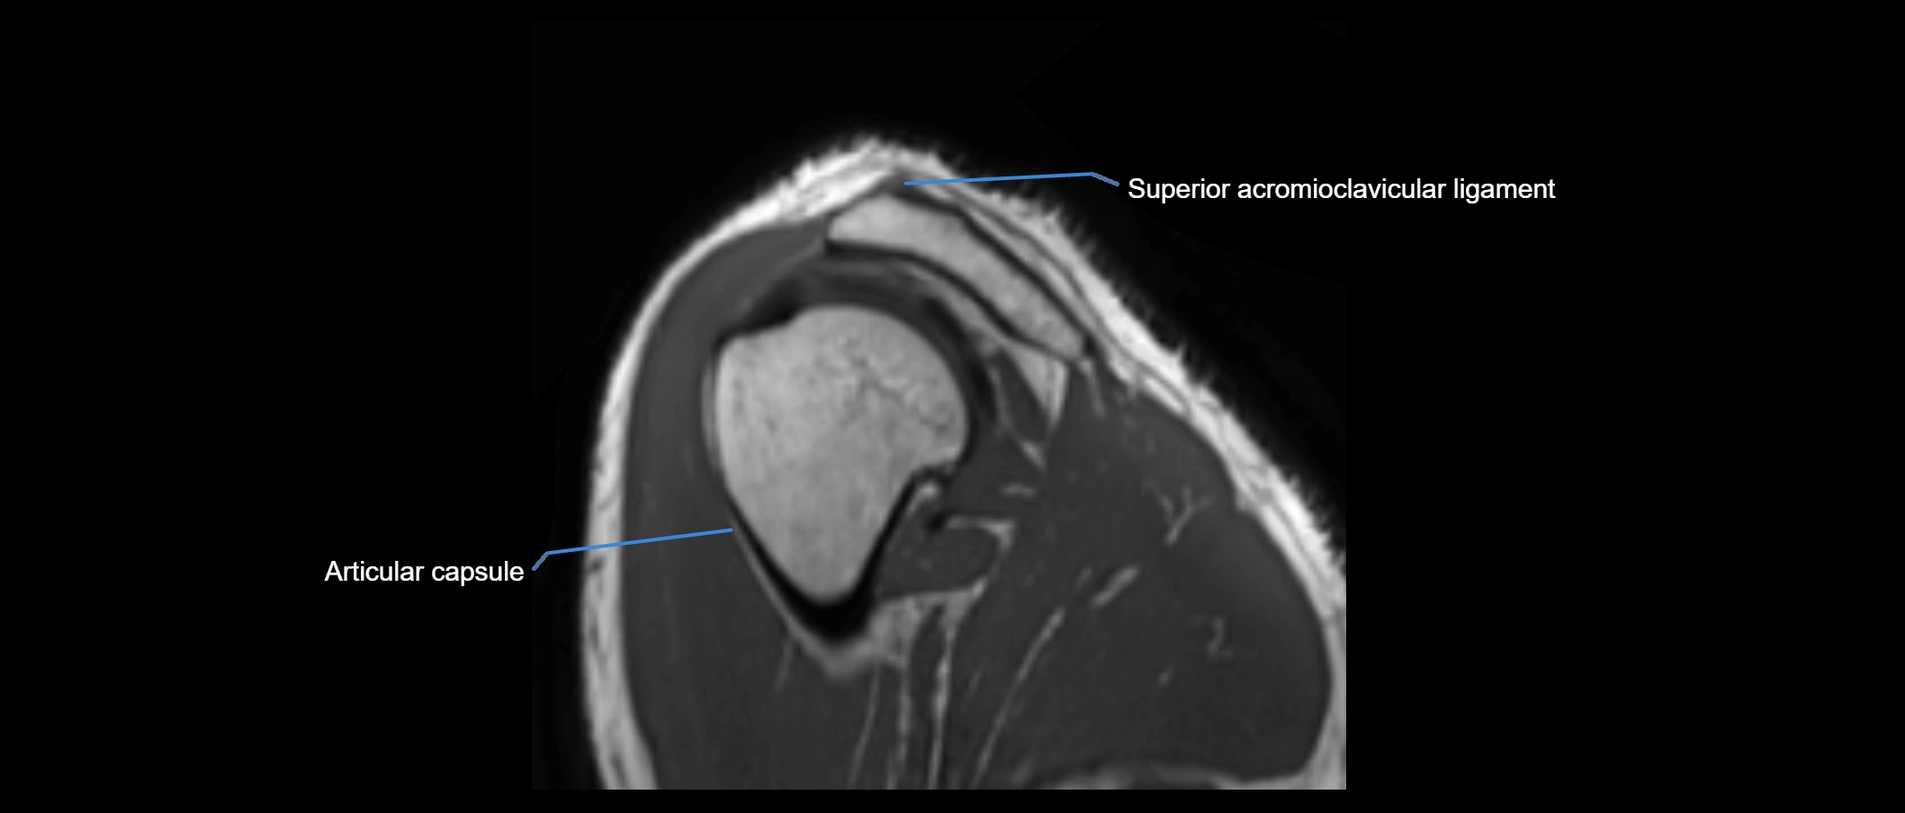

MRI images

image

MRI Appearance

• T1-weighted images:

• Normal ligament: Low signal (dark linear band) spanning acromion to clavicle.

• Surrounding fat planes: Bright, delineating the ligament clearly.

• Marrow of clavicle and acromion: Bright due to fatty content.

• Tears: Discontinuity or irregular thickening with intermediate-to-bright signal.

• Chronic injury: Thinning, fraying, or irregular low-signal fibers with adjacent scarring.

• T2-weighted images:

• Normal ligament: Low signal, homogeneous.

• Partial tear or sprain: Focal hyperintensity or thickening.

• Complete tear: Discontinuity with fluid-bright gap between clavicle and acromion.

• Associated edema: Bright signal in distal clavicle or acromion marrow.